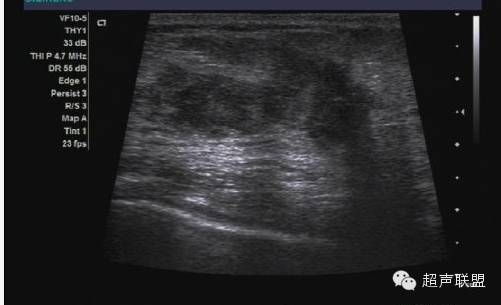

振荡多普勒成像或声学弹力图,是从著名的震颤乳腺超声技术派生而来的(如图5所示)。在震颤检查中,用彩色或功率多普勒进行乳腺成像的同时要求病人发出声音。乳腺中松软的部份振动较大,而癌变区域和其它较硬的组织振幅小,形成影像中色彩较弱的区域。这样原来在B超中声学特性一致的区域,因其结构的疏密变得可以区分。振荡弹力图或振荡多普勒成像与此类似,不同的是用一个单独的传感器产生振荡。该传感器可产生不同的振荡频率,而成像系统里的定量功率多普勒算法可以计算出组织在每一频率上的振荡量。振荡多普勒成像用于观察组织的粘弹特性。

对于20个病人的初步研究表明,病变区域的振荡量随频率变化的规律十分复杂。病变肿块区并不是在任一频率都会比周围组织振荡得小。这或许能够解释震颤法临床所得的结果变化不一。不同的病人发出不同的音调,在特定频率下,病变区的振荡不一定与周围组织不同。而且,良性肿块振荡量随频率变化的范围很大。相反癌变区表现出少量的振荡,而且随振荡频率的变化很小。